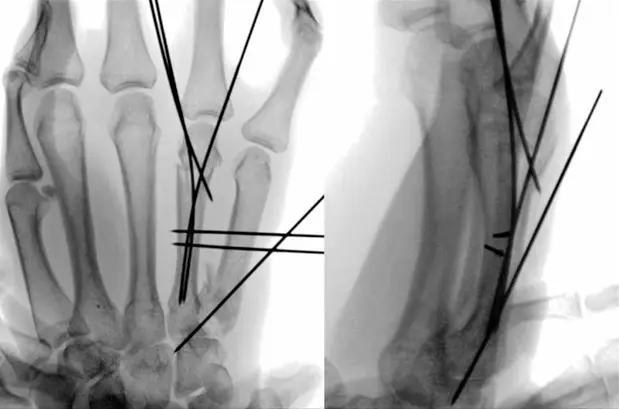

7. Percutaneous Intramedullary Fixation for First Metacarpal Base Fractures

Percutaneous Intramedullary Fixation.png